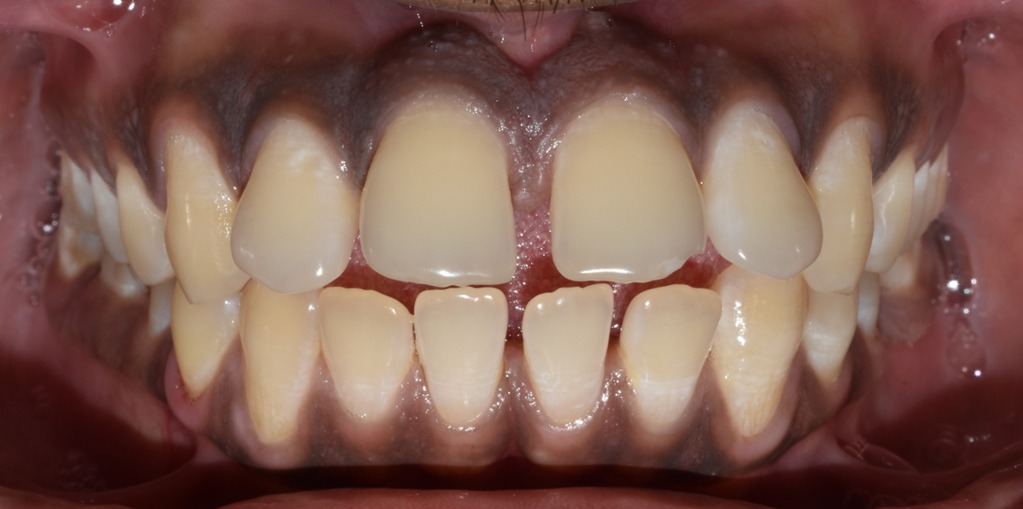

Before & After Results

At Aline Dent, we take pride in delivering visible and lasting improvements in our patients’ smiles. Our before-and-after results highlight the effectiveness of modern dental treatments combined with personalized care. This gallery showcases real dental cases treated at our clinic, giving you a clear idea of how different dental concerns can be corrected with the right treatment approach.

From minor corrections to complete smile enhancements, these teeth transformation results demonstrate how professional dental care can improve both oral health and appearance. Our experienced dental team carefully evaluates each patient’s needs and creates customized treatment plans to achieve natural, healthy, and confident smiles.

In this gallery, you will find a variety of smile makeover cases, including treatments for crooked teeth, gaps, discoloration, damaged teeth, and other common dental concerns.